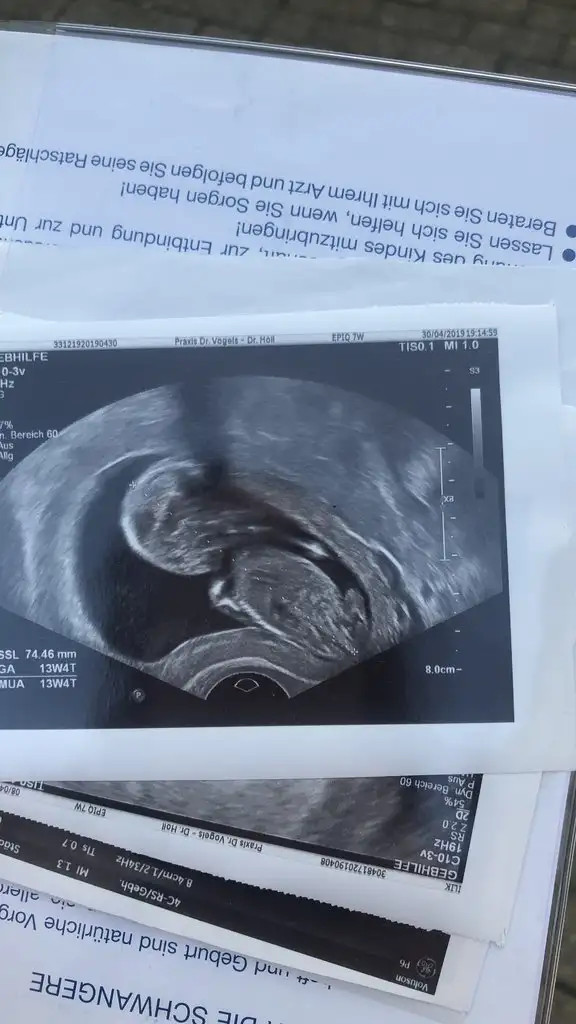

Iyi aksamlar kizlar ben yine en sona ciktim doktordan. Insan onu görünce unutuyor herseyi. 13 haftaydim tam bugün 13+5 cikti. Cinsiyeti de gördük. Pipi cikti karsimiza direk. O kadar bulanti hala devam ediyor demek kizla alakasi olmuyormus ögrenmis oldukhepimiz insallah saglikla kavusuruz

Hayırlı olsun canım ben belirtilere pek inanmıyorum bence herkese göre değişiyor.Bende tiksinme var ama hiç kusmadım Mahşallah. Belim ağrıyor bugün sol kasığım ağrıdı mesela. Değişiyor belirtiler bence.Iyi aksamlar kizlar ben yine en sona ciktim doktordan. Insan onu görünce unutuyor herseyi. 13 haftaydim tam bugün 13+5 cikti. Cinsiyeti de gördük. Pipi cikti karsimiza direk. O kadar bulanti hala devam ediyor demek kizla alakasi olmuyormus ögrenmis oldukhepimiz insallah saglikla kavusuruz

Belirtilere göre cinsiyet yormak gerçekten doğru çıkmıyor herkese göre değişiyor hep. Sağlıkla gelsin oğluşun inşallah hayırlı bi evlat olur inşallahIyi aksamlar kizlar ben yine en sona ciktim doktordan. Insan onu görünce unutuyor herseyi. 13 haftaydim tam bugün 13+5 cikti. Cinsiyeti de gördük. Pipi cikti karsimiza direk. O kadar bulanti hala devam ediyor demek kizla alakasi olmuyormus ögrenmis oldukhepimiz insallah saglikla kavusuruz